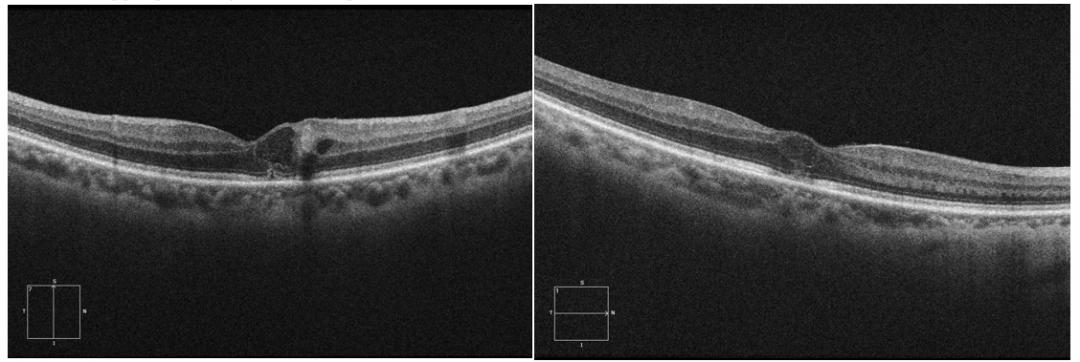

黄斑水肿oct图片,黄斑变性OCT读图

糖尿病性黄斑水肿的oct表现1)糖尿病性黄斑水肿4.

oct:右眼黄斑水肿较前稍好转iva第二针术后1个月复诊

患者黄斑oct图

眼底黄斑水肿的oct表现

黄斑水肿oct图片解释

黄斑水肿oct的详细图解